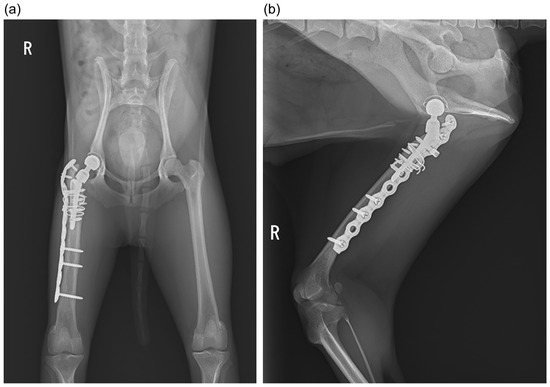

Figure 3.

Intraoperative photo taken at revision surgery. (a) A window was created by cutting the lateral cortex of the femur using a high-speed bur and an oscillating saw; (b) a stem that is one size larger (SN; proximal width of 3.9 mm; distal width of 2.8 mm) fixed to the femoral medial cortex; (c) the bone fragments were put back in the window and a plate and a cerclage wire was applied over them.

After stem removal, the femoral canal was reamed with a rasp to allow for the insertion of the SN stem with a proximal width of 3.9 mm and distal width of 2.8 mm, which can accommodate a body weight of up to 6 kg. A new stem was then placed to avoid the screw hole from the first surgery (Figure 3b). The bone fragment was placed back in the window and temporarily fixed with a 22 G stainless steel wire. A titanium plate was then placed externally from the femoral greater trochanter to the femoral diaphysis, and a cerclage wire was made with a 22 G stainless steel wire to secure the detached bone fragments (Figure 3c). The gap between the created window and the bone fragments was filled using bone allograft (Fortigen-p; Progenica, Duleek, Ireland). The hip joint was then repositioned after a new stem was attached to a size S neck and an 8 mm head. The surgical field was cleaned, sutured, and closed. Bacterial cultures performed around the implants at the beginning and end of the second surgery were negative. Postoperative medical therapy consisted of ceftazidime (25 mg/kg IV twice daily), meloxicam (0.1 mg/kg SC once daily), and famotidine (1 mg/kg IV once daily) These medications were continued for 7 days postoperatively. The dog was discharged on the 7th postoperative day and oral cephalexin (26 mg/kg orally twice daily) was administered for 7 days after discharge. Postoperative radiographs were obtained at 2, 4, 8, and 12 weeks, and then every 3 months until 1 year postoperatively (Figure 4). The patient was able to bear their weight and walk postoperatively, and the lameness resolved after approximately a month; a rehabilitation program was not necessary. Approximately 1 year after surgery, no lameness was observed; additionally, no findings suggestive of pain or a limited range of motion upon palpation were observed, and the radiographic examination did not reveal any issues.